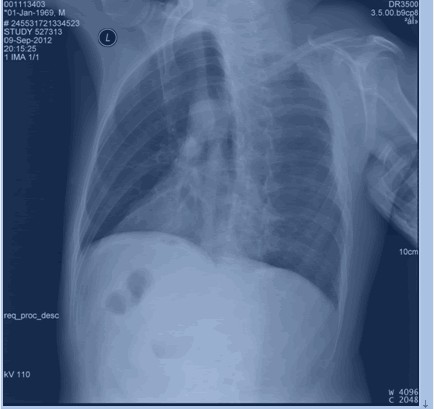

后肋骨折

圖示為右側3,5,6,7,8后肋骨折。

(2)斜位